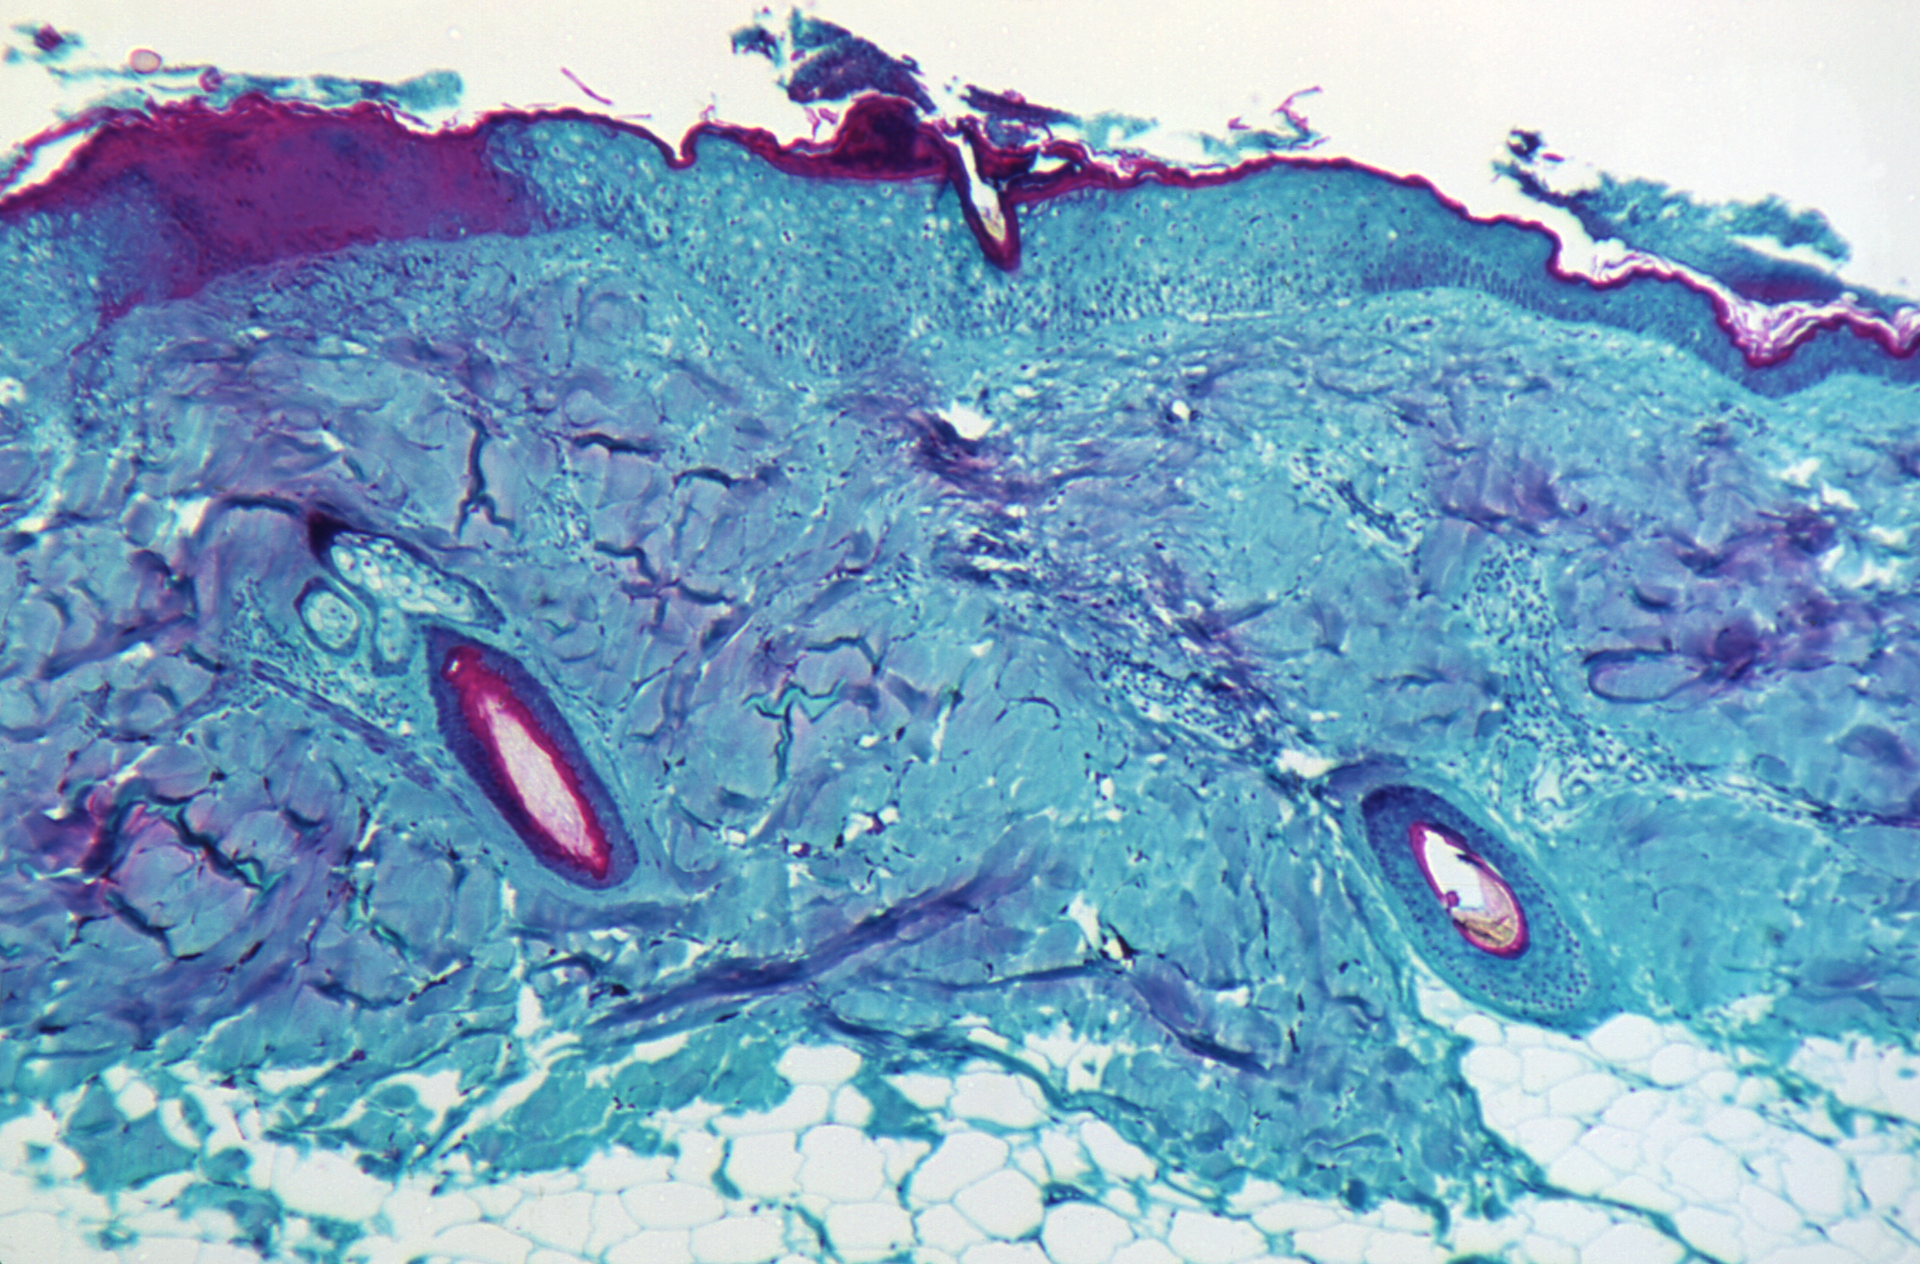

Monkeypox is a rare but potentially serious viral illness that typically begins with flu-like illness and swelling of the lymph nodes and progresses to a widespread rash on the face and body. Most infections last 2-4 weeks. Monkeypox is in the same family of viruses as smallpox but causes a milder infection. In this case, laboratory testing at CDC showed the patient is infected with a strain of monkeypox most commonly seen in parts of West Africa, including Nigeria. Infections with this strain of monkeypox are fatal in about 1 in 100 people. However, rates can be higher in people who have weakened immune systems.